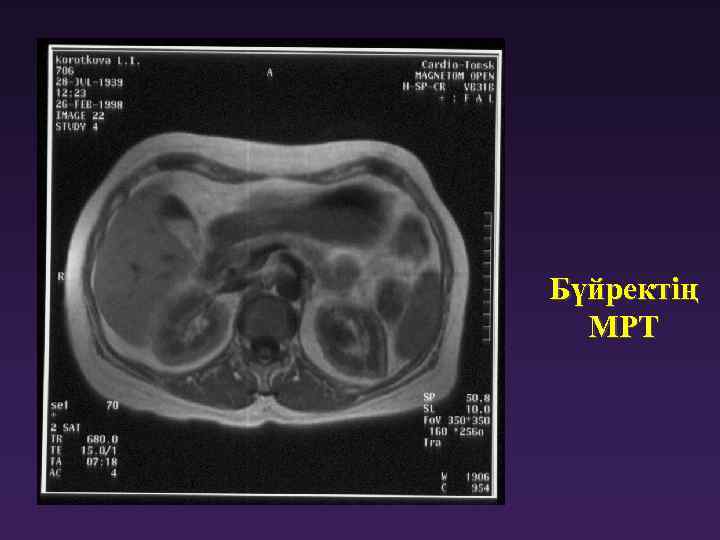

Бүйректің МРТ Көрсетулер: -Бүйрек дамуы аномалиясы - Бүйрек, бүйрекасты, кеуде кеңістігі ісіктері - Кисталар Бүйректің МРТ Көрсетулер: -Бүйрек дамуы аномалиясы - Бүйрек, бүйрекасты, кеуде кеңістігі ісіктері - Кисталар мен бүйрек ісіктерінің жіктелген диагностикасы - Бүйрек туберкулезі

Бүйректің МРТ Бүйректің МРТ